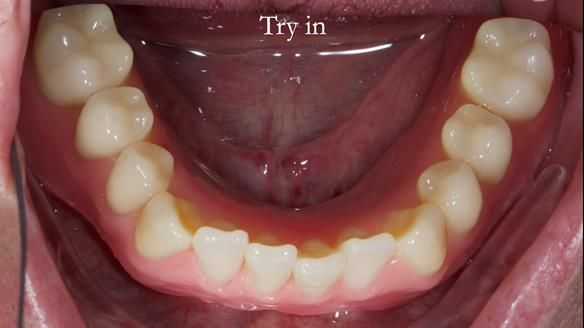

The detailed clinical situation and treatment process are outlined below, with clinical work provided by me and technical work by Rowan Garstang. New complete implant supported complete dentures were made. The new upper denture had ‘almost’ full palatal extension for the non-splinted implants following ITI guidelines. A decision was reached to retain the worn Kerator attachments, as their removal could potentially accelerate implant failure. The treatment spanned five visits for denture fitting and one review. Alisdair expressed great satisfaction with the treatment, noting a significant enhancement in his overall quality of life.